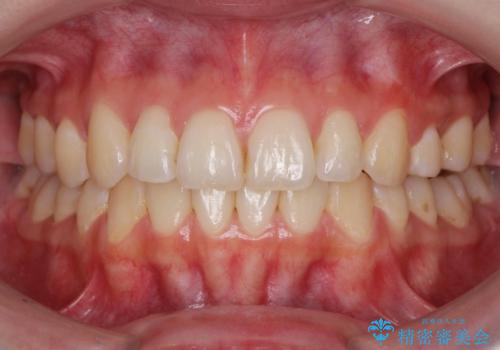

セラミッククラウンによる奥歯の修復

担当医 河口智英